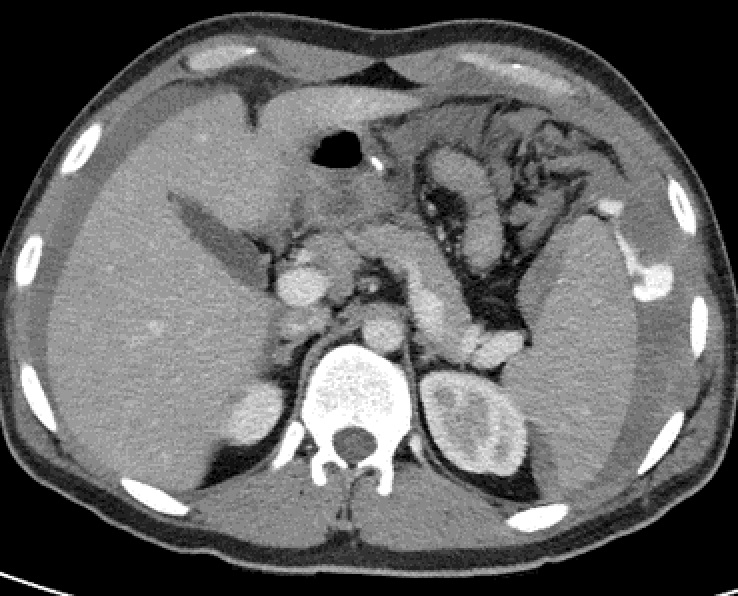

La TDM :

C'est la technique dominant dans

traumatisme splenique . la technique TDM avec

injection de contrast intraveineuse peut en utilise pour

explorer des extravasions de contrast lors de rupture des

vaissaux . Une extravasion de contrast par la dechirure des

vaissaux se donne de image de tres hyperdensite de 80 - 95

UH et aspect radiologique des traumatismes de la rate

peuvent variee selon au temps d'exposer ( arteriel ,

parenchymateux ou veineux ) . Les lacerations de la rate donne de image de ligne

hypodensite en forme geographique dans la rate . Aspect TDM

d'une hematome sous capsulaire est une zone de hypodensite

avec deformation d'allure et volumiseuse la rate .Hematome

intraparenchymateuse se donne de image de zone hypodense

dans la rate . Signe indirect de hemoperitoine peut en

s'observe sur la TDM

Aspect radiologique TDM d'une

traumatisme et contusion de la rate est image

hypodense lineaire ou en plage de mal limitees .

Image radiologique TDM d'une traumatisme de la rate

en coupe axiale et ẻn coup frontal |

Une autre traumatisme /

contusion de la rate est image hypodense en plage un

partie anterieure - interieure de la rate . Image radiologique

TDM en coupe axiale |